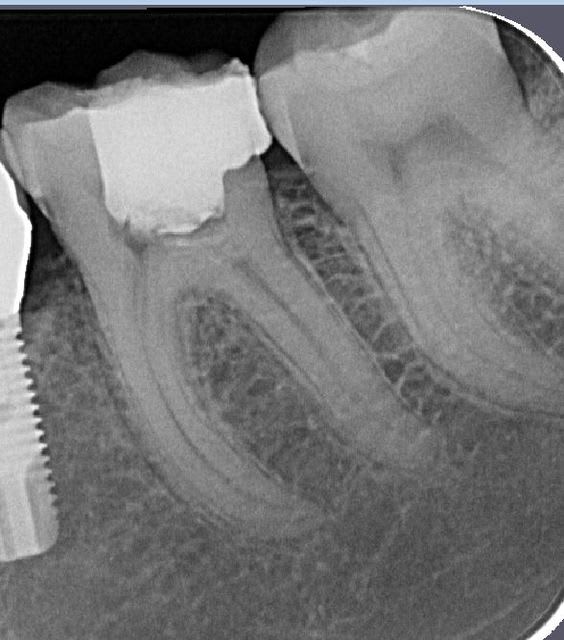

sur cette dent vous faites bio + inlay

ou alors, qui fait une CCC ?

Je tenterais l'onlay . (+endo)

Si t'arrives à faire ton endo sans élargir plus la chambre, c'est une indication d'Inlay.

Mais il y a fort à parier au regard de la courbure importante de la racine mésiale qu'il faudra élargir cette chambre en mésiale, à ceci s'ajoute une carie débutante toujours en mésiale (sans parler des caries multiples un peu partout), donc on se dirige à mon avis vers de la prothèse périphérique.

la limite distale finira en juxta osseux.non?

on peux quand meme faire un inlay?

Je privilégierai l'inlay sauf si ça le fait pas une fois la carie nettoyée.

Il y a de bonnes parois dentaires, ça me ferait mal au coeur de les supprimer.

L'émail perdu complique un peu l'inlay-onlay.

1er choix inlay-onlay, 2e choix ccc, pas de tenon métal ou de IC.

Ceux qui font un "inlay", pourquoi pas plutôt un composite direct ?